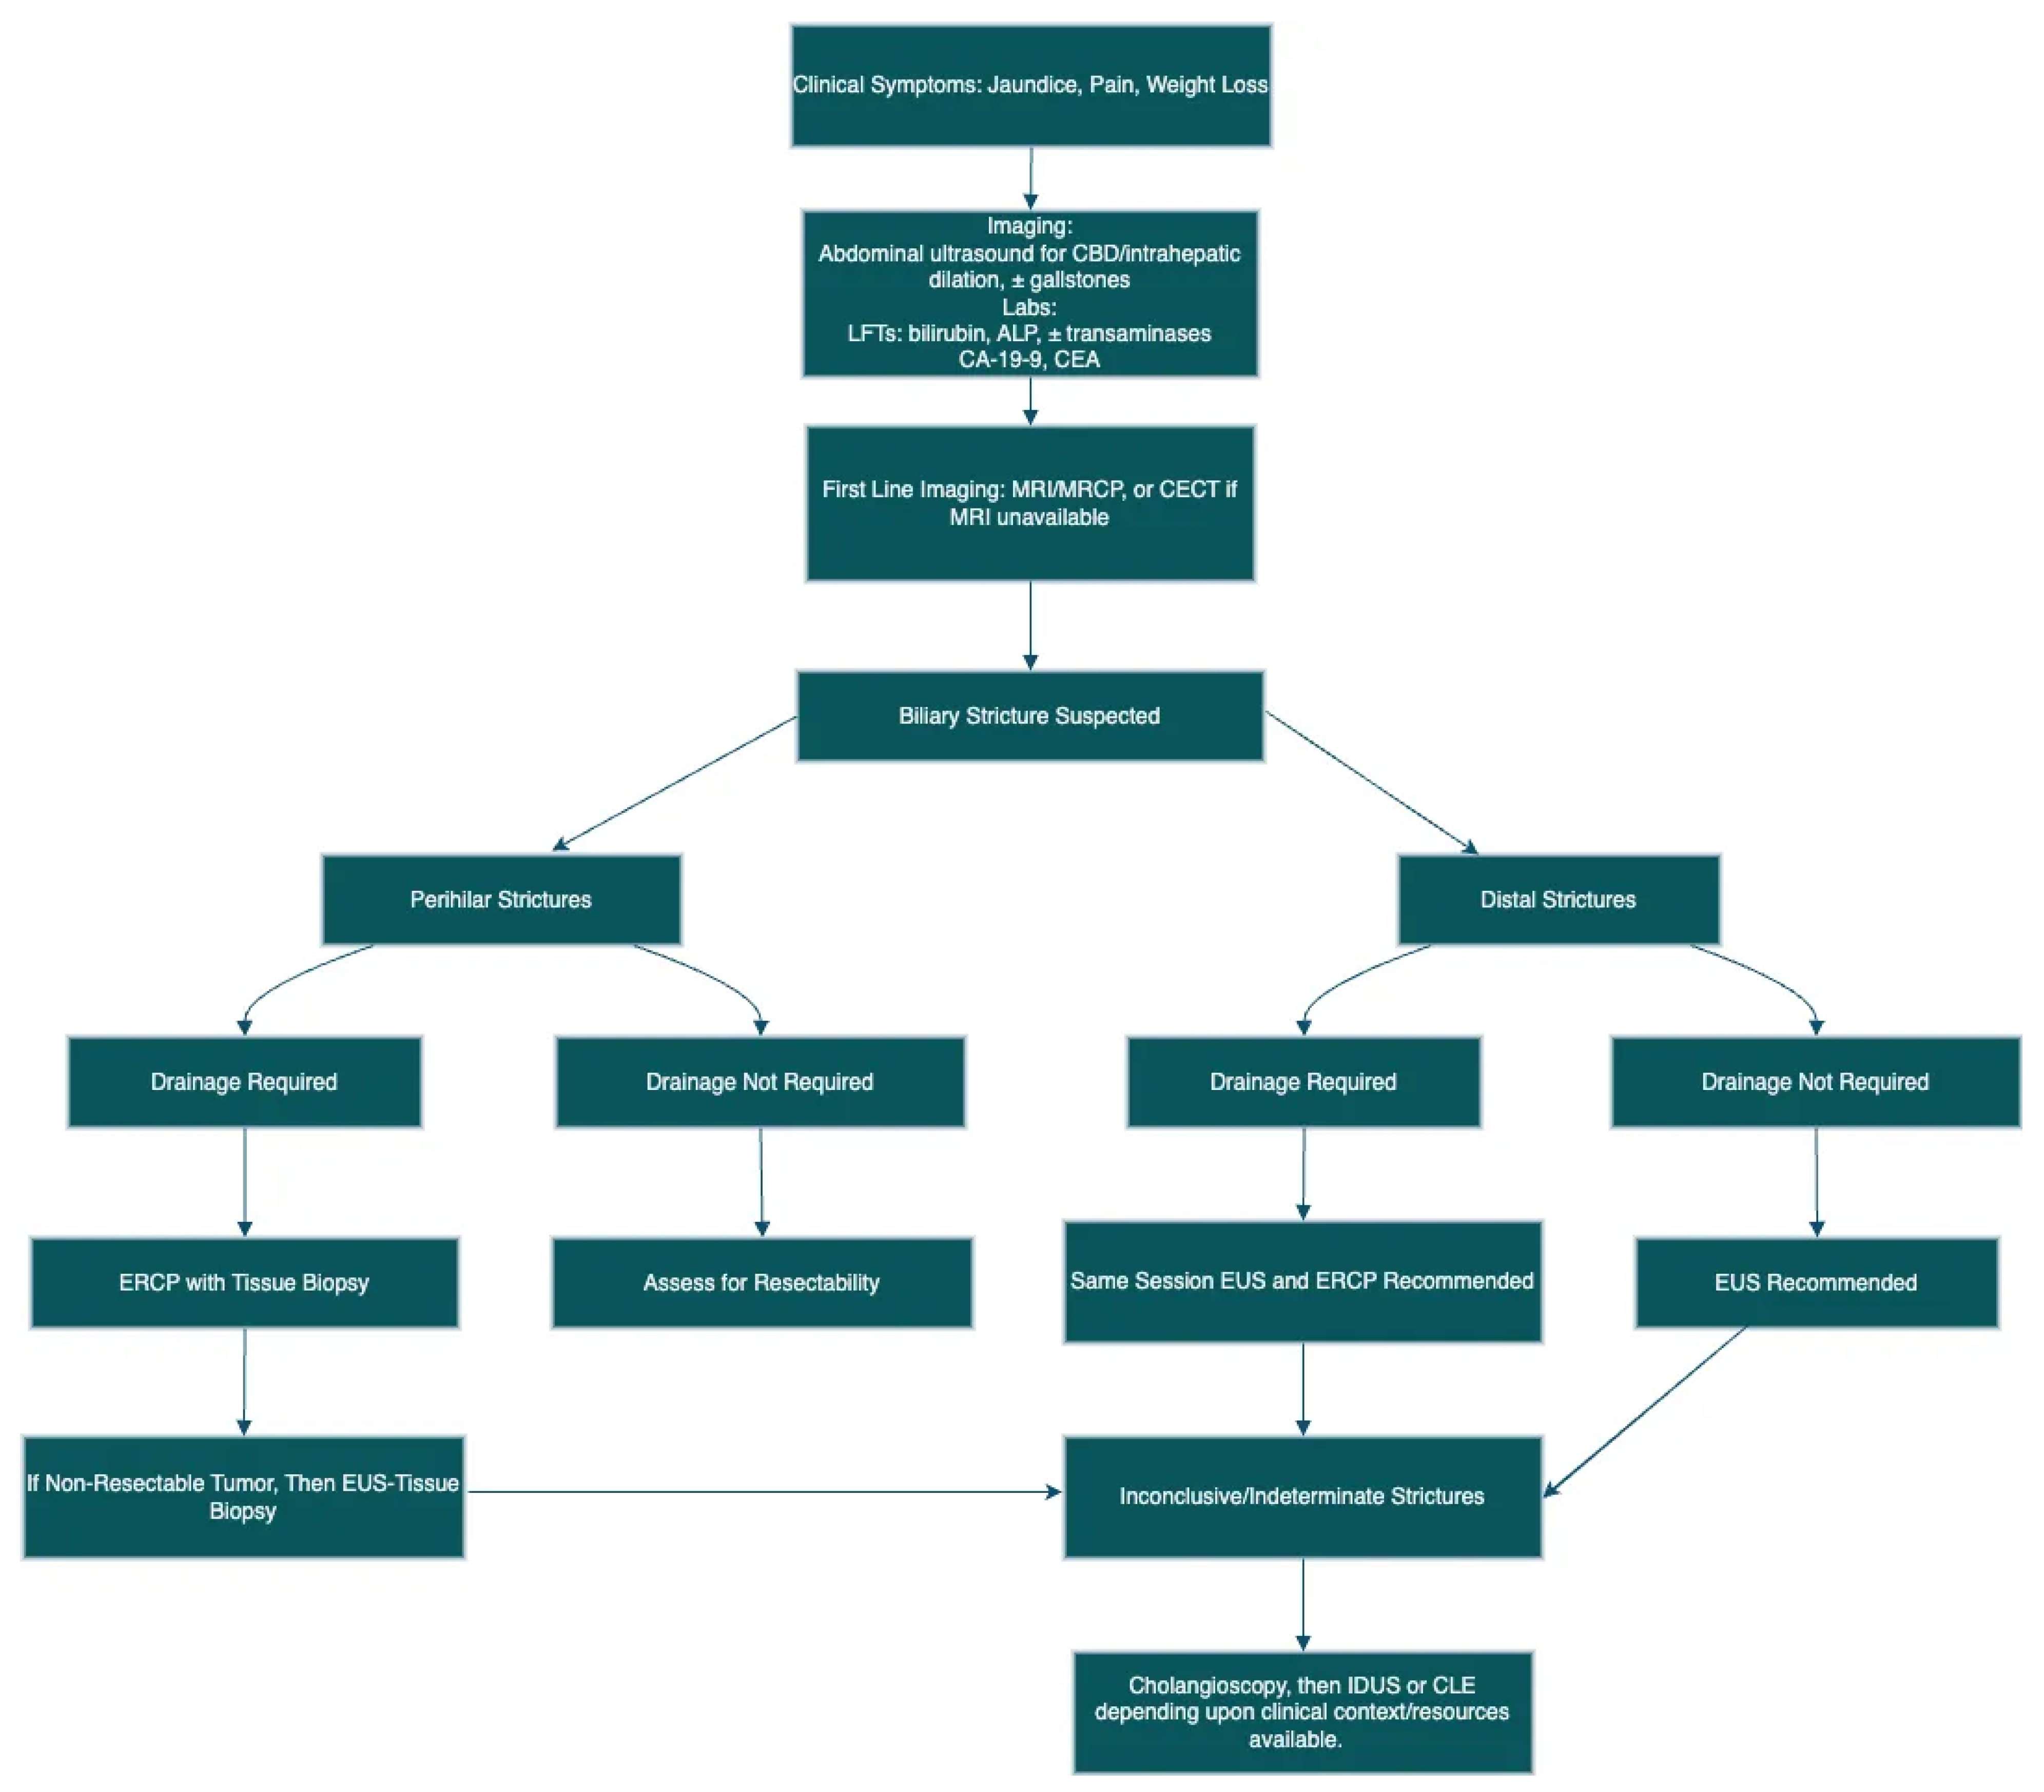

5.1. Extrahepatic Strictures

5.2. Perihilar Structures

5.3. Indeterminate Biliary Strictures